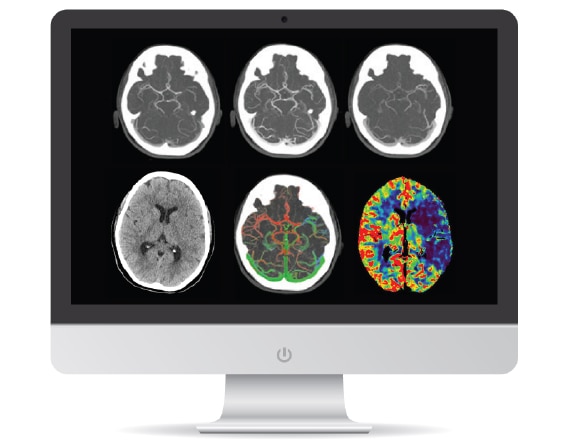

РЕШЕНИЯ В ОБЛАСТИ ЛЕЧЕНИЯ ИНСУЛЬТА